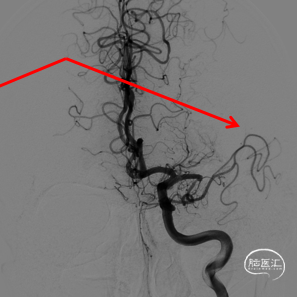

2、直接释放自膨支架:✔

优点:支撑性强,如一次重建良好,可显著简化操作,避免夹层撕裂风险。

缺点:可能存在残余血栓或狭窄。做好后扩准备。

支架导管确认真腔

静脉维持基础上3ml替罗非班动脉推注,4.5*20 EZ(手头无EP)

支架输送导丝,路途显示残留狭窄,跟进支架导管备后扩

3m导丝支架内成袢通过

导丝到位后即刻造影

观察后血流变差

2.0*10白驹跟进困难,更换1.5*15

10atm扩张,血流维持差

2.0*10白驹通过顺利

打起后原位维持2分钟

“天又亮了”